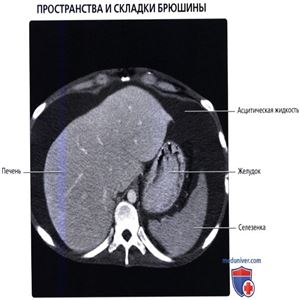

КТ с контрастированием, исследование мужчины среднего возраста с циррозом и очерченными пространствами и складками брюшины, представлены первые четыре аксиальных среза. Асцитическая жидкость расширяет брюшинную полость, способствуя визуализации углублений и складок брюшины, не наблюдающихся в норме.

Сальниковая сумка и брюшинная полость расширены асцитической жидкостью. Желудочно-селезеночная связка и поджелудочная железа образуют границу сальниковой сумки, как и малый сальник, положение которого обозначается воротной веной и чревным стволом.

Серповидная связка поддерживает печень с передней брюшной стенки. Большой сальник лежит между кишечником и передней брюшной стенкой.

Внутрибрюшинные органы, такие как печень, поперечно-ободочная кишка и тонкая кишка взвешены в асцитической жидкости, при этом она не влияет на положение забрюшинных органов, таких как почки и поджелудочная железа.